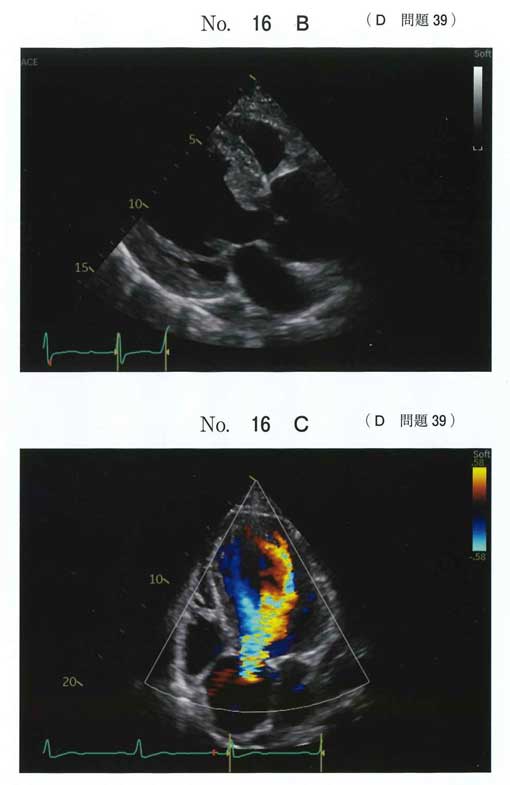

正解: a

大動脈弁+上行大動脈基部を同時に置換が必要

→ Bentall手術が適応

b 僧帽弁置換:病変なし

c 大動脈弁置換単独:大動脈拡張が残る

d 上行大動脈置換単独:ARが残る

e TAVI:AR・大動脈基部拡張では不適

ARと大動脈基部の拡張という明らかな誘導ありBentallしかないだろう。